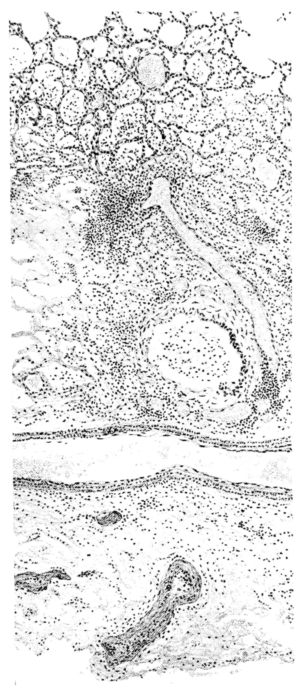

FIG. III. AUTOPSY NO. 90. DRAWING FROM A LESION OF THE TRACHEA (SOMEWHAT OLDER THAN THAT ILLUSTRATED IN FIGURE II). THE MUCOSA IS ENTIRELY LACKING. CONGESTION AND EDEMA ARE THE STRIKING FEATURES IN THE SUBMUCOSA. THE NECROTIZING PROCESS HAS EXTENDED INTO THE MUCUS GLANDS. THIS IS SHOWN IN THE LOWER PICTURE.

FIG. IV. AUTOPSY NO. 205. CONGESTION AND EDEMA OF THE SUBMUCOSA AND REGENERATION OF THE TRACHEAL EPITHELIUM.

The changes are less marked, perhaps, in the trachea than in its finer ramifications. The mucosa is constantly more or less destroyed and large areas, usually focal, are entirely devoid of their epithelial covering. This is replaced by a sparse exudate, composed largely of red blood cells, mucus, a small amount of fibrin, and nuclear fragments (Fig. II). It may dip into the submucosa for a short distance, but usually these indentures are associated with the ducts of the mucous glands into which the inflammatory reaction extends. A more striking feature than the exudate, however, is the edema and the congestion of the submucosa. The loose areolar tissue of the submucosa is spread widely apart, and throughout it distended blood vessels are very conspicuous. Occasionally such a vessel is broken and actual hemorrhage appears in the submucosa. Occasionally, too, the inflammation extends down the duct to the mucous gland itself, and here, also, aplastic inflammatory reaction is evident, inasmuch as the acini now stain intensely red with the cells undifferentiated from each other and specked here and there by broken remains of the dead nuclei (Fig. III). After the disease has continued for a short period, even at the end of five or six days, some regeneration of the epithelial lining may be seen (3) (Fig. IV). But despite this, the acute picture persists, and there goes on, side by side, an attempted repair characterized by epithelial regeneration and the same evidence of acute change. Since the lesion is essentially a superficial one, scars or contractures of any extent are not encountered in the trachea, even in examples of the disease that have ended fatally only after many weeks.[4]